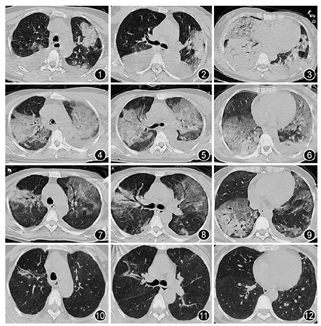

✓ 干咳无痰却胸痛难忍(易误诊为肺炎)